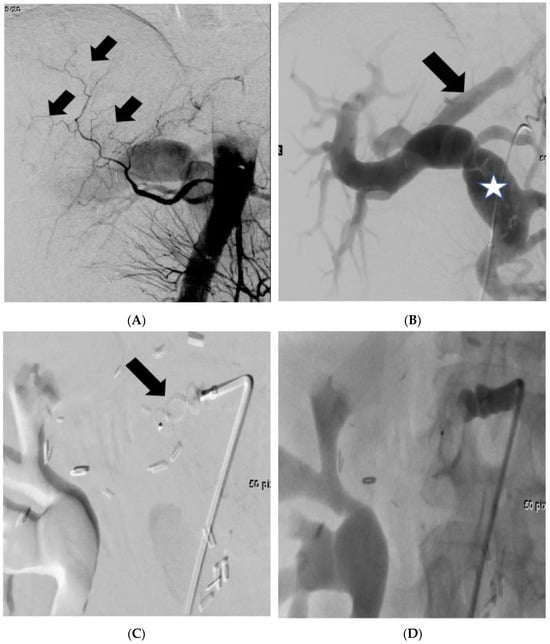

2. Methods and Results

Patient Information